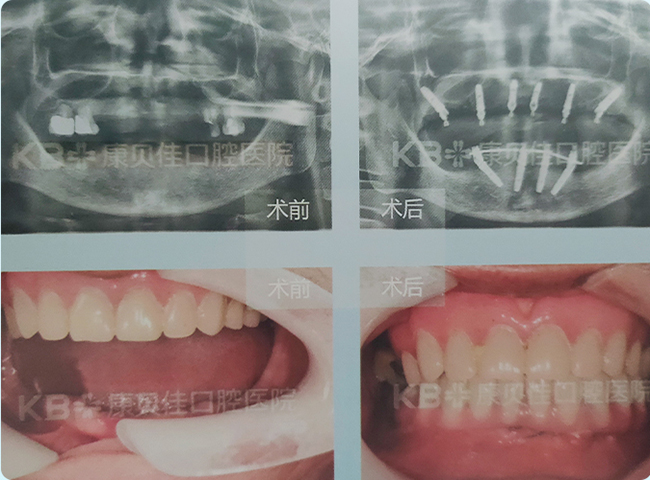

曲女士 55岁

全口多颗牙缺失30余年,多颗牙做过根管治疗。后牙区吃饭用不上力。找到任博士要求种植。 任博士通过即拔即种、缺多种少的方式,恢复了患者上下后牙区的咬合关系,重建了一口好牙。

治疗方案:

上颌种植5颗恢复6颗 下颌种植2颗